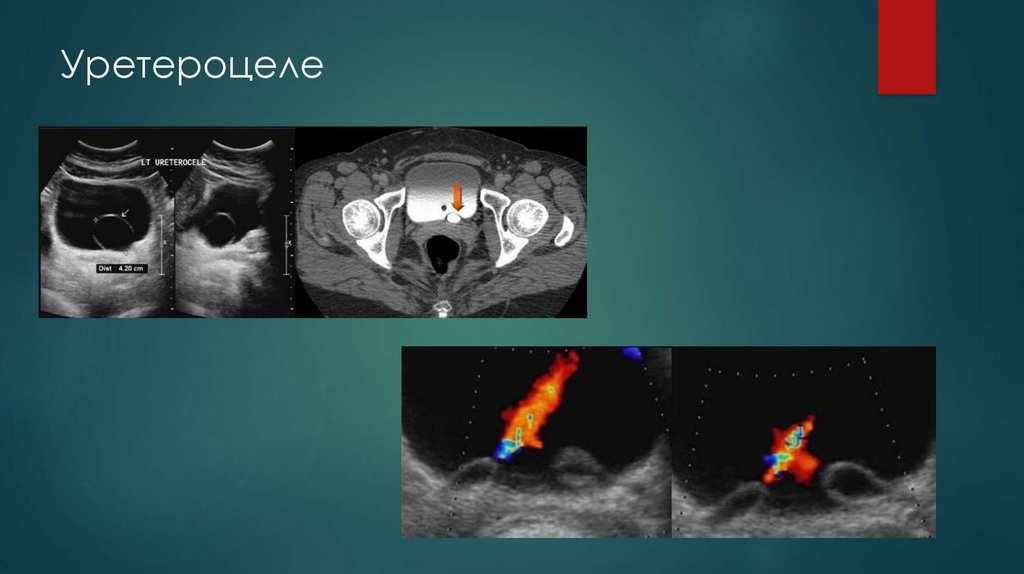

Уретероцеле